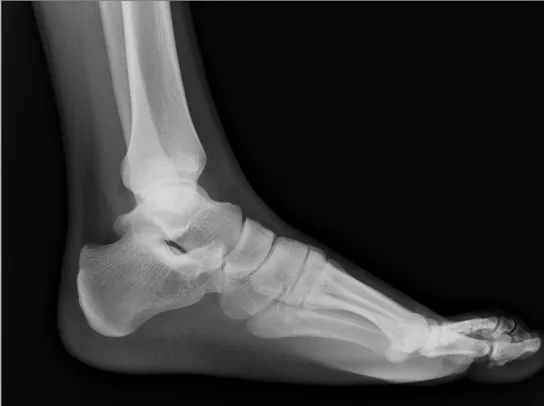

X-ray of foot You likely think of your bones as part of a system, connected to one another by joints. Sesamoids are exceptions to this rule, ‘free floating’ bones that offer a smooth surface for your tendons to slide over, creating a sort of pulley system for the muscles. The sesamoids in your feet help you as you walk, and without them, your big toe would lose some of its power and force. Sesamoiditis itself is pain or inflammation of the sesamoids.